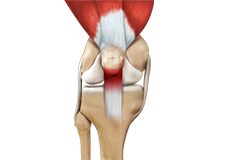

Patellar Tendon Rupture

The patellar tendon works together with the quadriceps muscle and the quadriceps tendon to allow your knee to straighten out. Patella tendon rupture is the rupture of the tendon that connects the patella (kneecap) to the top portion of the tibia (shinbone).

Patellar Tendinitis

Patellar tendinitis, also known as "jumper's knee", is an inflammation of the patellar tendon that connects your kneecap (patella) to your shinbone. This tendon helps in extension of the lower leg.